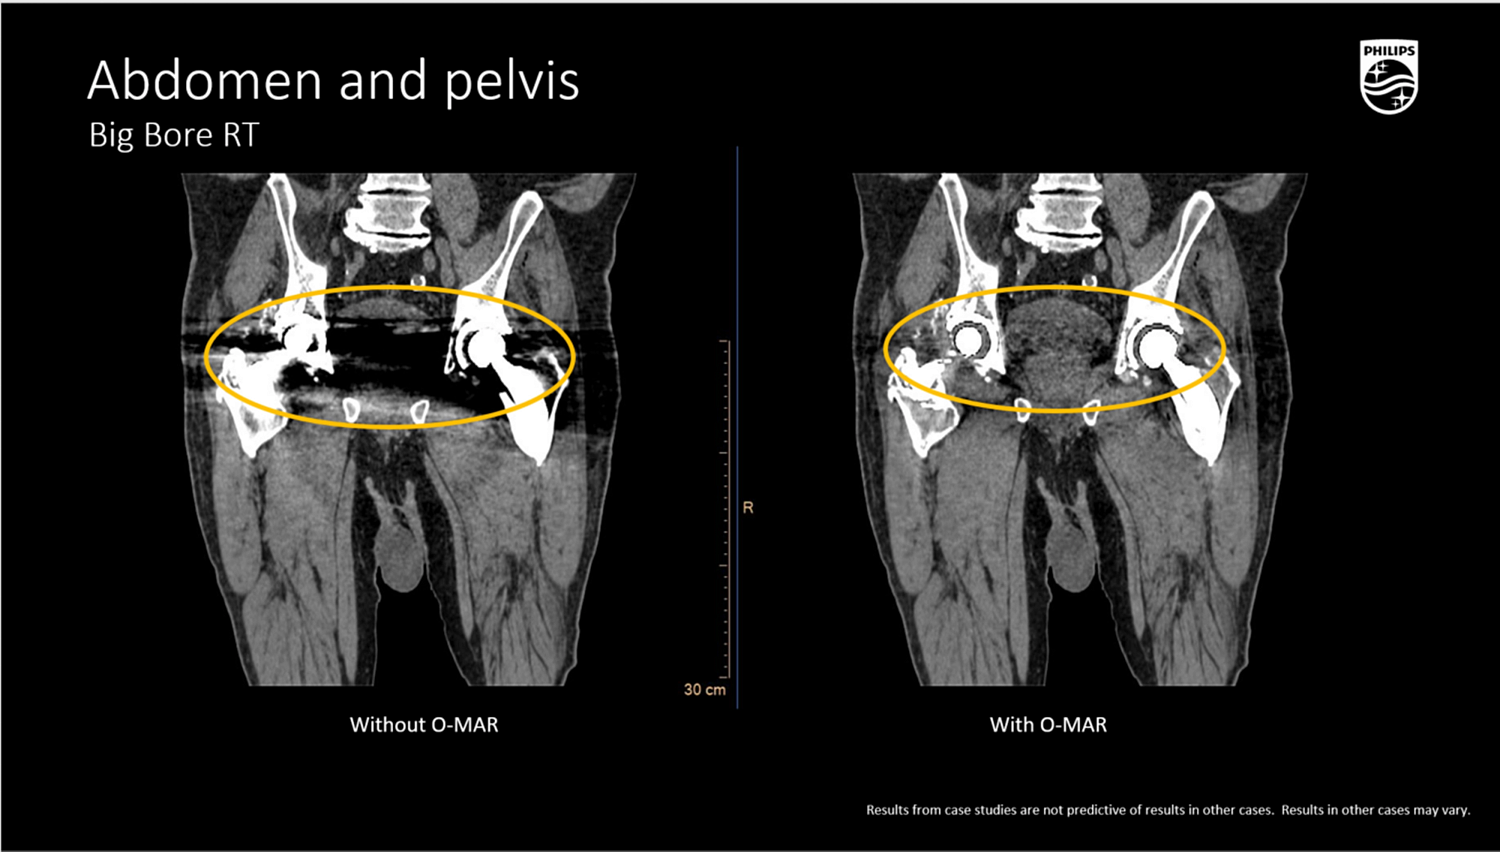

O-MAR (Orthopedic Metal Artifact Reduction)

- Комплексный алгоритм для снижения артефактов от эндопротезов, спиц, хирургических скоб и зондов,

- Существенно повышает точность КТ-контурирования в условиях металлоиндуцированных искажений, что критично для радиотерапии позвоночника и малого таза.